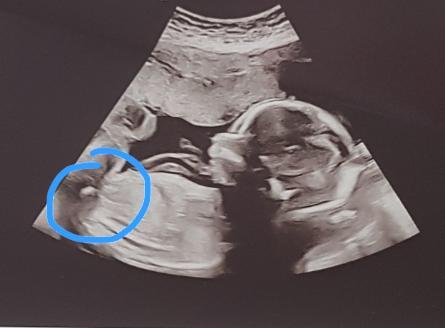

Crazykat21 · 04/04/2020 18:16

@Menarefrommarsitwouldseem can I please ask if you can tell me what this is please? Is it the cord, or girl/boy parts? 🤔 23weeks1day

I'm a sonographer/radiographer- ask me anything.

The pregnancy scan I would say boy. Probably too late now Haha but that's what I think. I don't do obstetrics though so could be wrong.